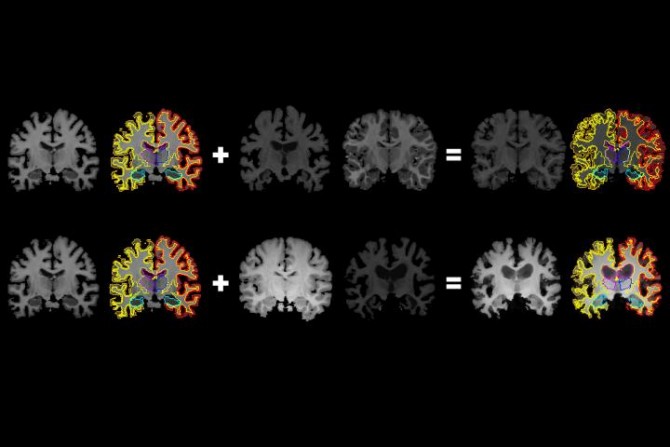

MIT researchers have developed a system that gleans far more labeled training data from unlabeled data, which could help machine-learning models better detect structural patterns in brain scans associated with neurological diseases. The system learns structural and appearance variations in unlabeled scans, and uses that information to shape and mold one labeled scan into thousands of new, distinct labeled scans. (Credit: Amy Zhao/MIT)

In generating a new scan, the system applies a random flow field to the original labeled scan, which shifts around voxels until it structurally matches a real, unlabeled scan. Then, it overlays a random intensity transformation. Finally, the system maps the labels to the new structures, by following how the voxels moved in the flow field. In the end, the synthesized scans closely resemble the real, unlabeled scans -- but with accurate labels.